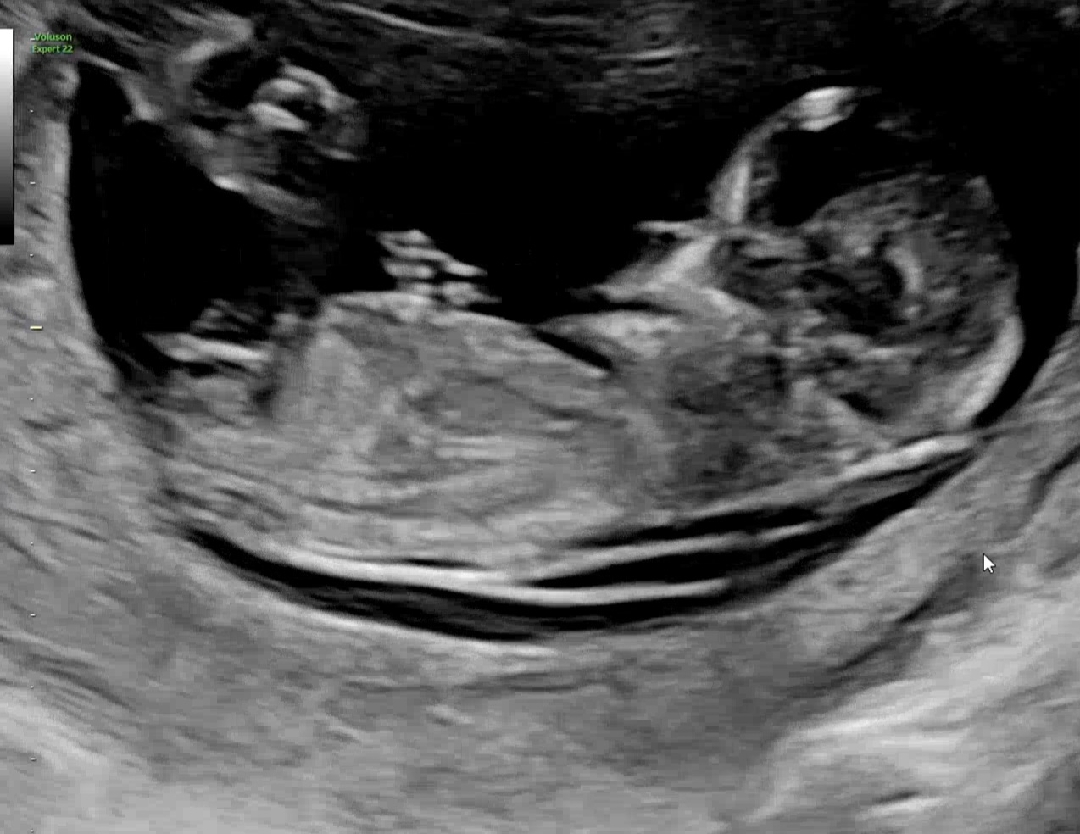

12주차 각도법!!

둘째라 더 궁금하네요 ㅠㅠ 지나치지마시궁 참견 부탁드려요